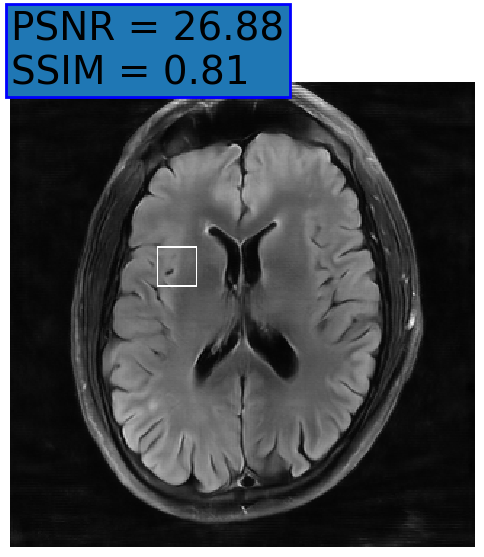

5.2 Uncertainty Assessment

We calculated the mean value of the std. maps, obtained by our method and the Monte Carlo Dropout method, for all images in the inference set and utilized it as an uncertainty measure. The correlation between these uncertainty measures and reconstruction error (MSE) is depicted in Fig. 4. Our NPB-REC uncertainty measure exhibits a higher correlation with the Reconstruction error compared to Dropout (Pearson correlation coefficient of r=0.93𝑟0.93r=0.93 vs. r=0.89𝑟0.89r=0.89). Further, fig. 4LABEL:sub@fig3:c demonstrates our uncertainty measures correlate better with the acceleration rates used during acquisition. These outcomes, in turn, indicate the ability of our uncertainty measure to detect unreliable reconstruction performance. It is worth mentioning that the strong linearity of the correlation exhibited was preserved even for higher acceleration rates and when we repeated the same experiments on the knee test set (in all cases we obtained r>0.92𝑟0.92r>0.92).